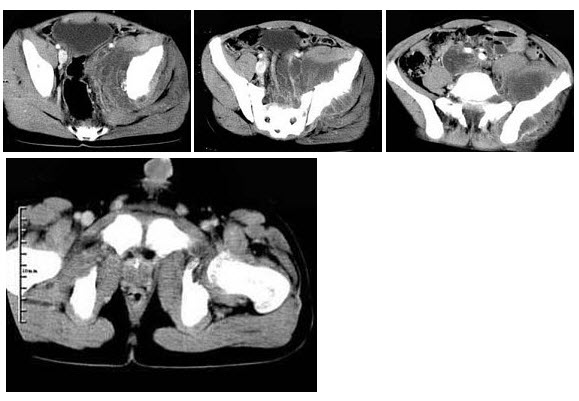

230、单项选择题

女,35岁,7月前无诱因出现左下肢阵发性疼痛,左骶髂部活动受限,进行性加重,排便困难,根据所提供的图像,最可能的诊断是()

A.脊索瘤

B.软骨肉瘤

C.骨巨细胞瘤

D.转移瘤

E.滑膜肉瘤